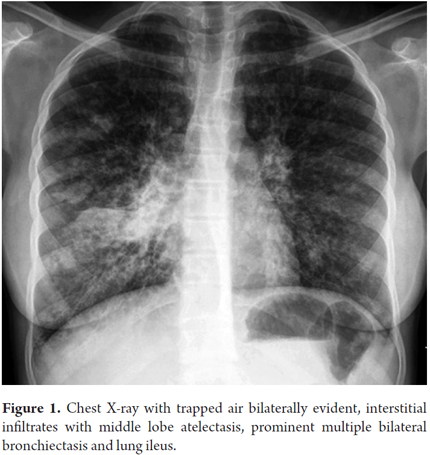

The patient was a 12 year mestiza girl who had been diagnosed with CF at 2 years of age. She had been colonized by pseudomonas aeruginosa but had no history of meconium ileus. She came to the clinic after 15 days of fever, coughing, dyspnea and orthopnea. During the review of her systems the patient reported occasional abdominal pain and constipation (hard stools every 2 days). She was hospitalized for treatment of pulmonary exacerbation with cefepime and amikacin. Gram staining and a culture of her sputum showed pseudomonas aeruginosa that was resistant to cefepime, so the antibiotic therapy was modified to replace it with ciprofloxacin. An anteroposterior chest x-ray showed bilateral bronchiectasis and atelectasis of the middle lobe (Figure 1). A high resolution CT scan and total abdominal ultrasound of the chest confirmed this finding (Figure 2). chocardiography revealed mild pulmonary hypertension.